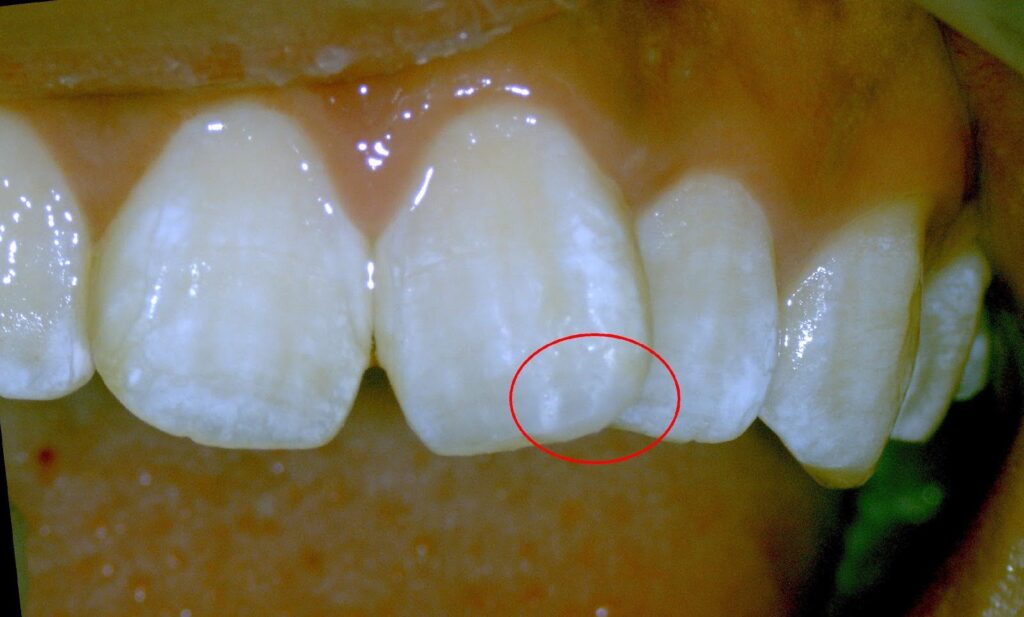

赤丸が膿んでいる病変部